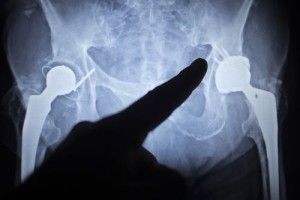

While typical hip implants consist of components made of metal and plastic, the Biomet Magnum has three all-metal components: a metal femoral head, metal taper insert and metal acetabulum cup.

As the metal parts rub against each other, microscopic shavings of metal may be released into the hip joint, which could cause inflammation, loosening, and other problems associated with metal hip poisoning.